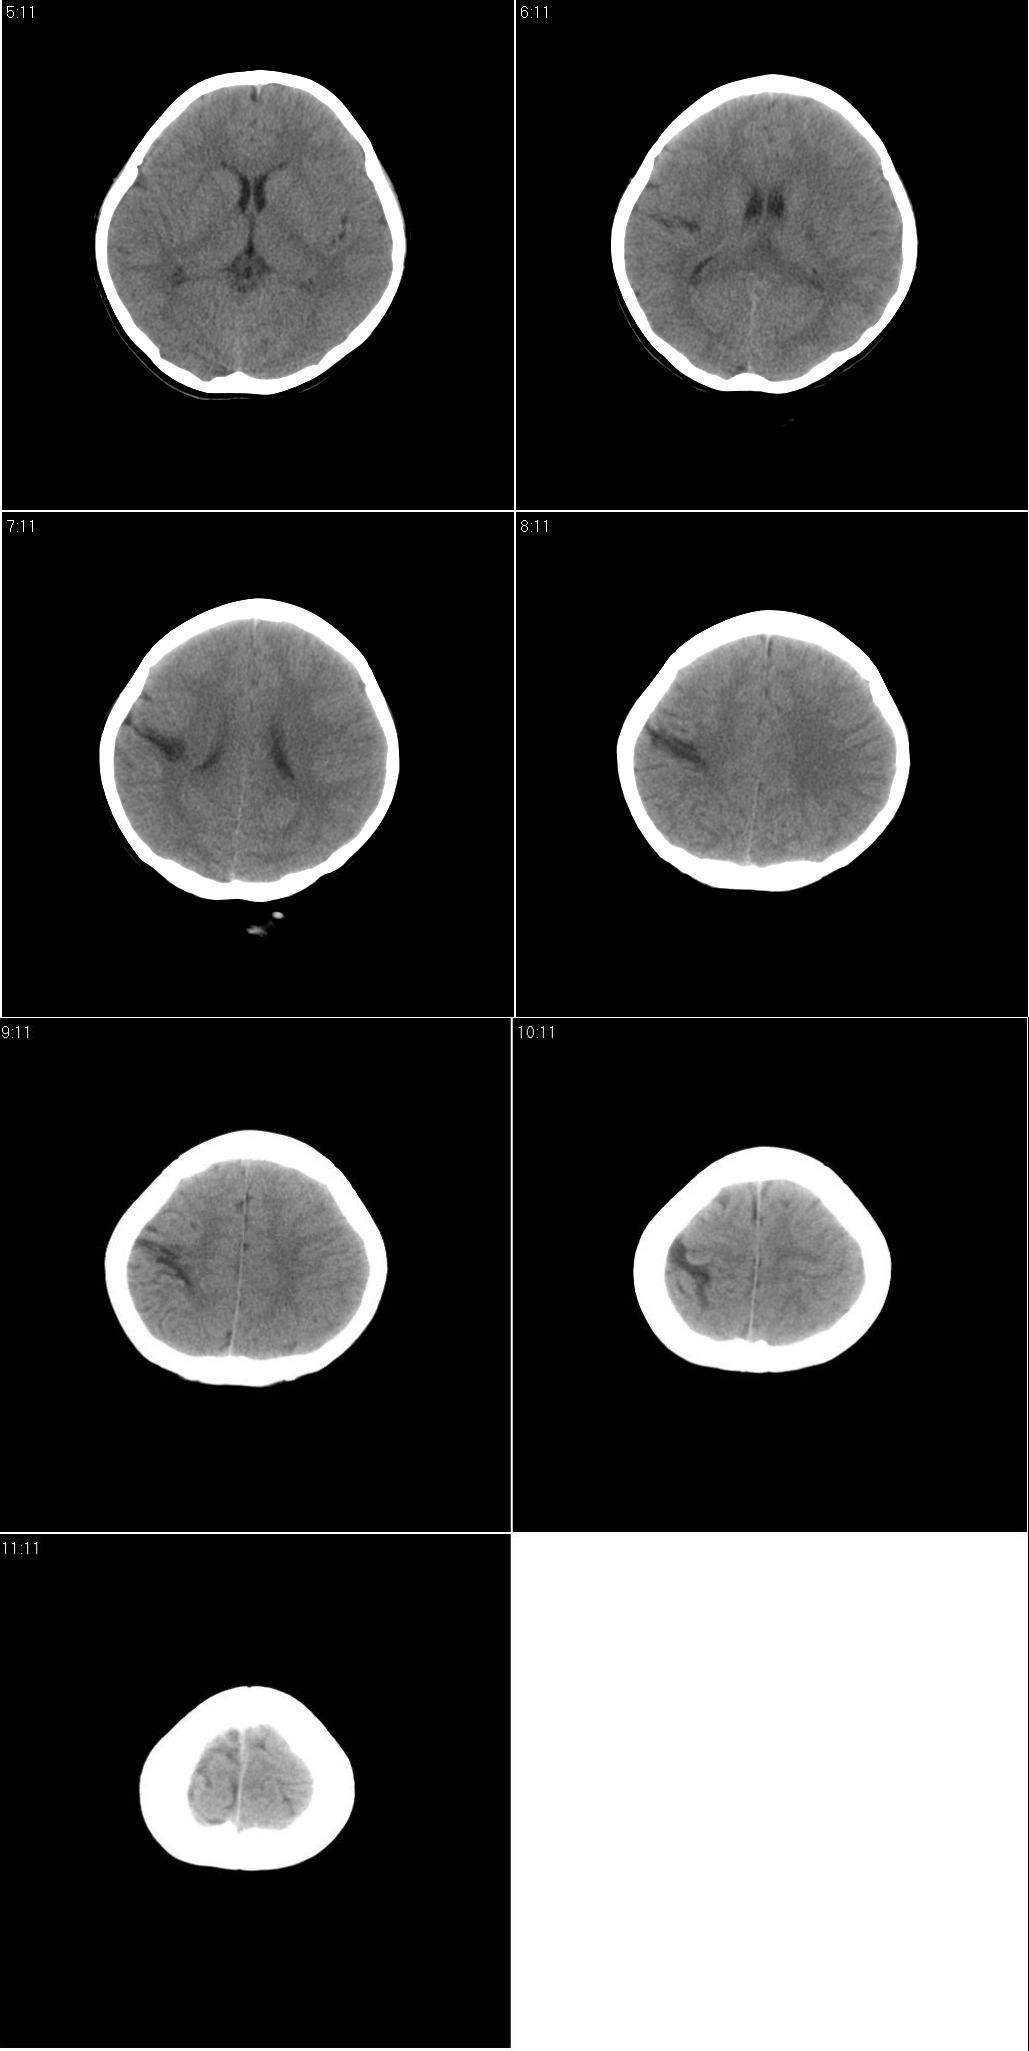

标题: PED1643:女,10岁。抽风两次。 [打印本页]

标题: PED1643:女,10岁。抽风两次。

右侧大脑皮质裂隙,未与脑室相通,应该是脑裂畸形。

主要与脑穿通畸形相鉴别。两者相同点:都是跨越大脑半球的裂隙。不同点:脑裂畸形有皮层灰质沿裂隙内折到脑室壁。穿通畸形:裂隙两缘无皮层内折。脑裂畸形一定合并灰质异位。但灰质异位不一定合并脑裂畸形。

右侧脑裂畸形,灰质异位

右侧脑裂畸形,灰质异位 脑穿通畸形囊肿常有负占位 。

病灶形态及与脑表面的关系,临近脑皮质形态及临近脑沟形态较支持脑裂畸形伴临近脑皮质发育不良,但辐射冠及半卵圆中心层面示病灶与白质间无明显灰质内称,这个不太符合脑裂畸形,因此脑裂畸形首先考虑不除外脑穿通畸形

考虑脑裂畸形.软化灶或穿通畸形应该有相应的脑沟裂增宽,侧脑室扩大

右侧脑裂畸形.{闭合型}